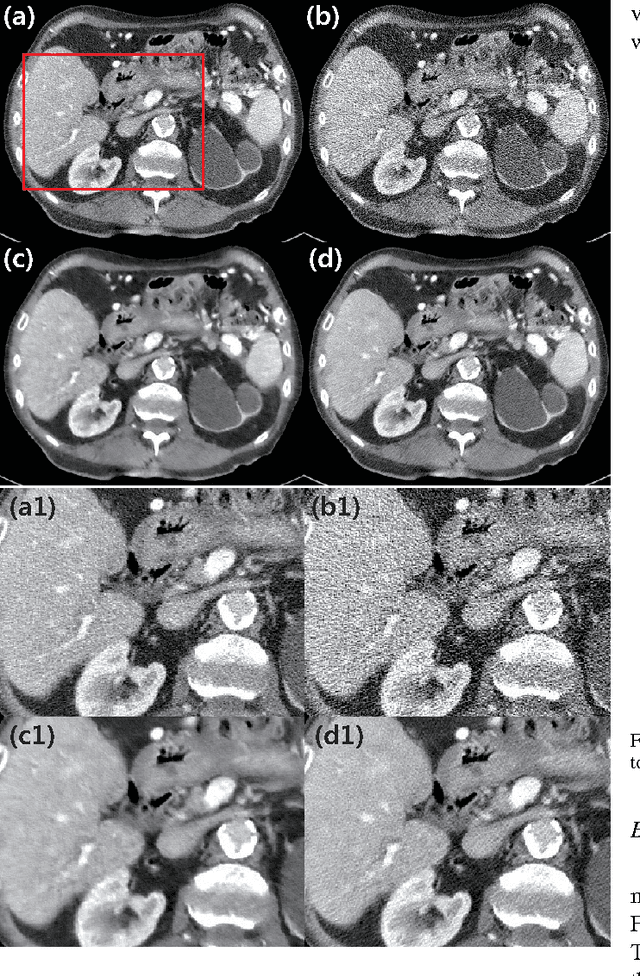

Abstract:Due to the potential risk of inducing cancers, radiation dose of X-ray CT should be reduced for routine patient scanning. However, in low-dose X-ray CT, severe artifacts usually occur due to photon starvation, beamhardening, etc, which decrease the reliability of diagnosis. Thus, high quality reconstruction from low-dose X-ray CT data has become one of the important research topics in CT community. Conventional model-based denoising approaches are, however, computationally very expensive, and image domain denoising approaches hardly deal with CT specific noise patterns. To address these issues, we propose an algorithm using a deep convolutional neural network (CNN), which is applied to wavelet transform coefficients of low-dose CT images. Specifically, by using a directional wavelet transform for extracting directional component of artifacts and exploiting the intra- and inter-band correlations, our deep network can effectively suppress CT specific noises. Moreover, our CNN is designed to have various types of residual learning architecture for faster network training and better denoising. Experimental results confirm that the proposed algorithm effectively removes complex noise patterns of CT images, originated from the reduced X-ray dose. In addition, we show that wavelet domain CNN is efficient in removing the noises from low-dose CT compared to an image domain CNN. Our results were rigorously evaluated by several radiologists and won the second place award in 2016 AAPM Low-Dose CT Grand Challenge. To the best of our knowledge, this work is the first deep learning architecture for low-dose CT reconstruction that has been rigorously evaluated and proven for its efficacy.